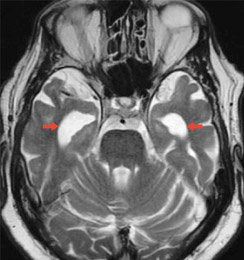

mri_alzheimer_untypisch

Abb. 2a

Standard-MR-Bild eines Patienten mit Demenzerkrankung: untypischer Bildbefund für eine Alzheimer-Erkrankung, ohne Aufweitung der Hirnkammern (rote Pfeile)